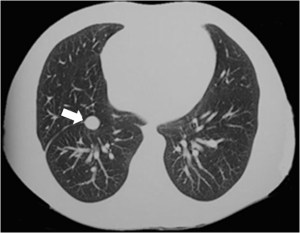

SIGNO DE LA CISURA INCOMPLETA, DE LA PSEUDOCAVIDAD O SIGNO DE LA ESPINA DE ROSA

Es un signo de derrame pleural en la cisura mayor visible en la radiografía de tórax, en un paciente con cisura mayor incompleta. Es más frecuente verlo en el lado derecho ya que en el izquierdo la silueta cardiaca puede ocultarlo.

La presencia de una zona radiotransparente perihiliar, circunscrita lateralmente por una línea curva bien marcada (flecha blanca), en cuya periferia se observan varios grados de opacidad, corresponde a la presencia de líquido en la cisura mayor incompleta. La línea curva termina en un extremo en punta (flecha roja), que estará más cercana al hilio cuanto más completa sea la cisura.

El nombre de pseudocavidad hace referencia a la radiolucencia perihiliar, mientras que el de espina de la rosa se refiere a la morfología de la opacidad, con el extremo en punta.